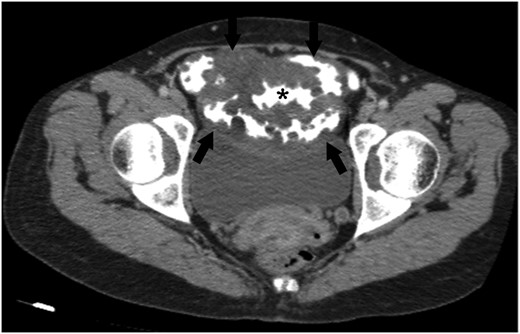

CT showed increased wall thickness on 40 cm segment of ileum. Capsule endoscopy was performed and a polypoid infiltrating area was found ~40–50 cm segment of middle and distal jejenum (Fig. 2A and B). Bone marrow biopsy was performed for suspicious lymphoproliferative disease. Biopsy result showed normocellular bone marrow. Flow cytometry of bone marrow mononuclear cells with the work done by immunophenotyping detected no significant antigenic exploration. It was decided to take a PET-CT for to clarify a suspicious tumor or paraneoplastic syndrome in patient. PET-CT showed diffuse wall thickness increase in the ileum. These results are in line with the assessment of the causes of protein-losing enteropathy; lymphangiectasia, intestinal lymphoma and tuberculosis. After all, surgical decision was taken with these presumptive diagnoses.

An axial CT image obtained with intravenous and oral contrast material shows abnormal wall thickening of ileal loops (arrows). Please note that the multiple nodular formations of ileal wall protruding the contrast-filled intestinal lumen (*). Abdominal CT scan also demonstrates a mass-like diffuse expansion of mesenteric root with low attenuation (arrows).